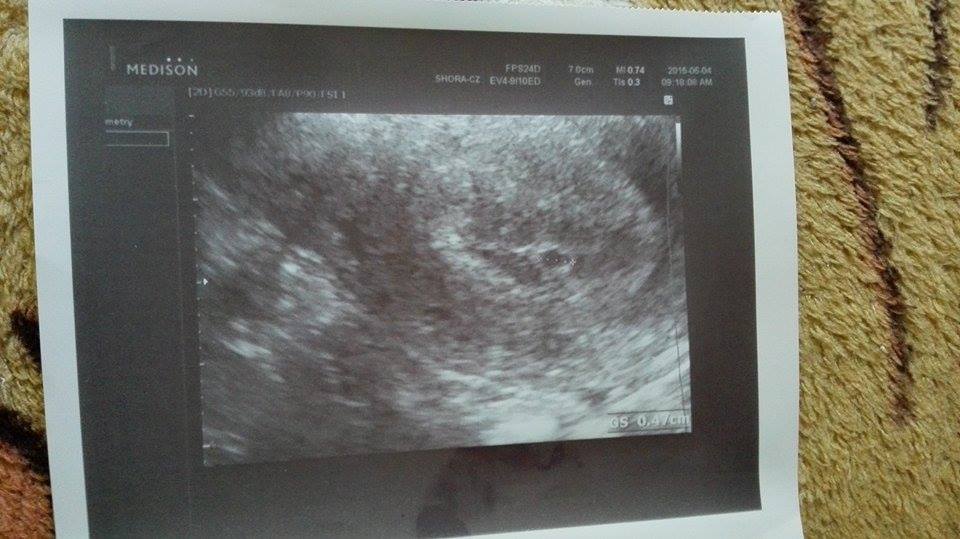

Ahoj holky v sobotu sem měla cca 3-4 dny zpoždění zkusila sem test a vyšel žádný duch prostě o trošku slabší čárka než ta hlavní.V pondělí na utz nic , ale nyblo vidět tak mi bral krev a potvrdil těhot. říkal za týden se stavte . Ale jelikož je 30 km z bývalého bydliště m tak jsem dnes volala jinému co sídlí kousek od baráku tady kde ted žiji. A říkal at se zastavím , tak se bojím , že je ještě brzo když v pondělí nic nebylo co myslíte dělala sem test i dneskaprostě jistota jestli stoupá a je skoro čárka jak hlavní jak uschla je stejná. Tak se bojím trochu, protože mě postrašil , že pokud to neuvidí může to být i mimoděložní , že jako to mi musí říct , že to tak říká všem , protože až budu víc že se ujistíme

První fotečkaa